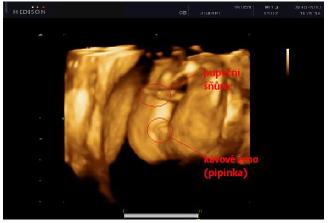

30.03. - (20+5), tak na dnešní kontrole dopadlo všechno na 1*, vážíme už 380g a z našeho Marečka se nakonec vyklubala Amálka, která měla mezi nožičkama zamotenej pupečník 😀 Pan doktor říkal, že tentokrát, je to opravdu na 100%